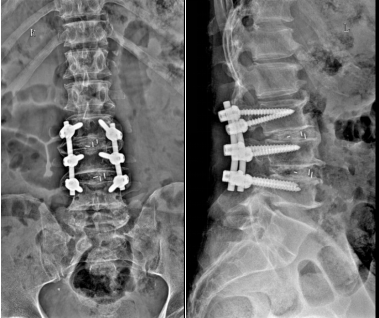

术后腰椎正侧位示腰椎前凸恢复良好

王大爷术后5天即可直立行走,长高了8CM,对手术效果十分满意。